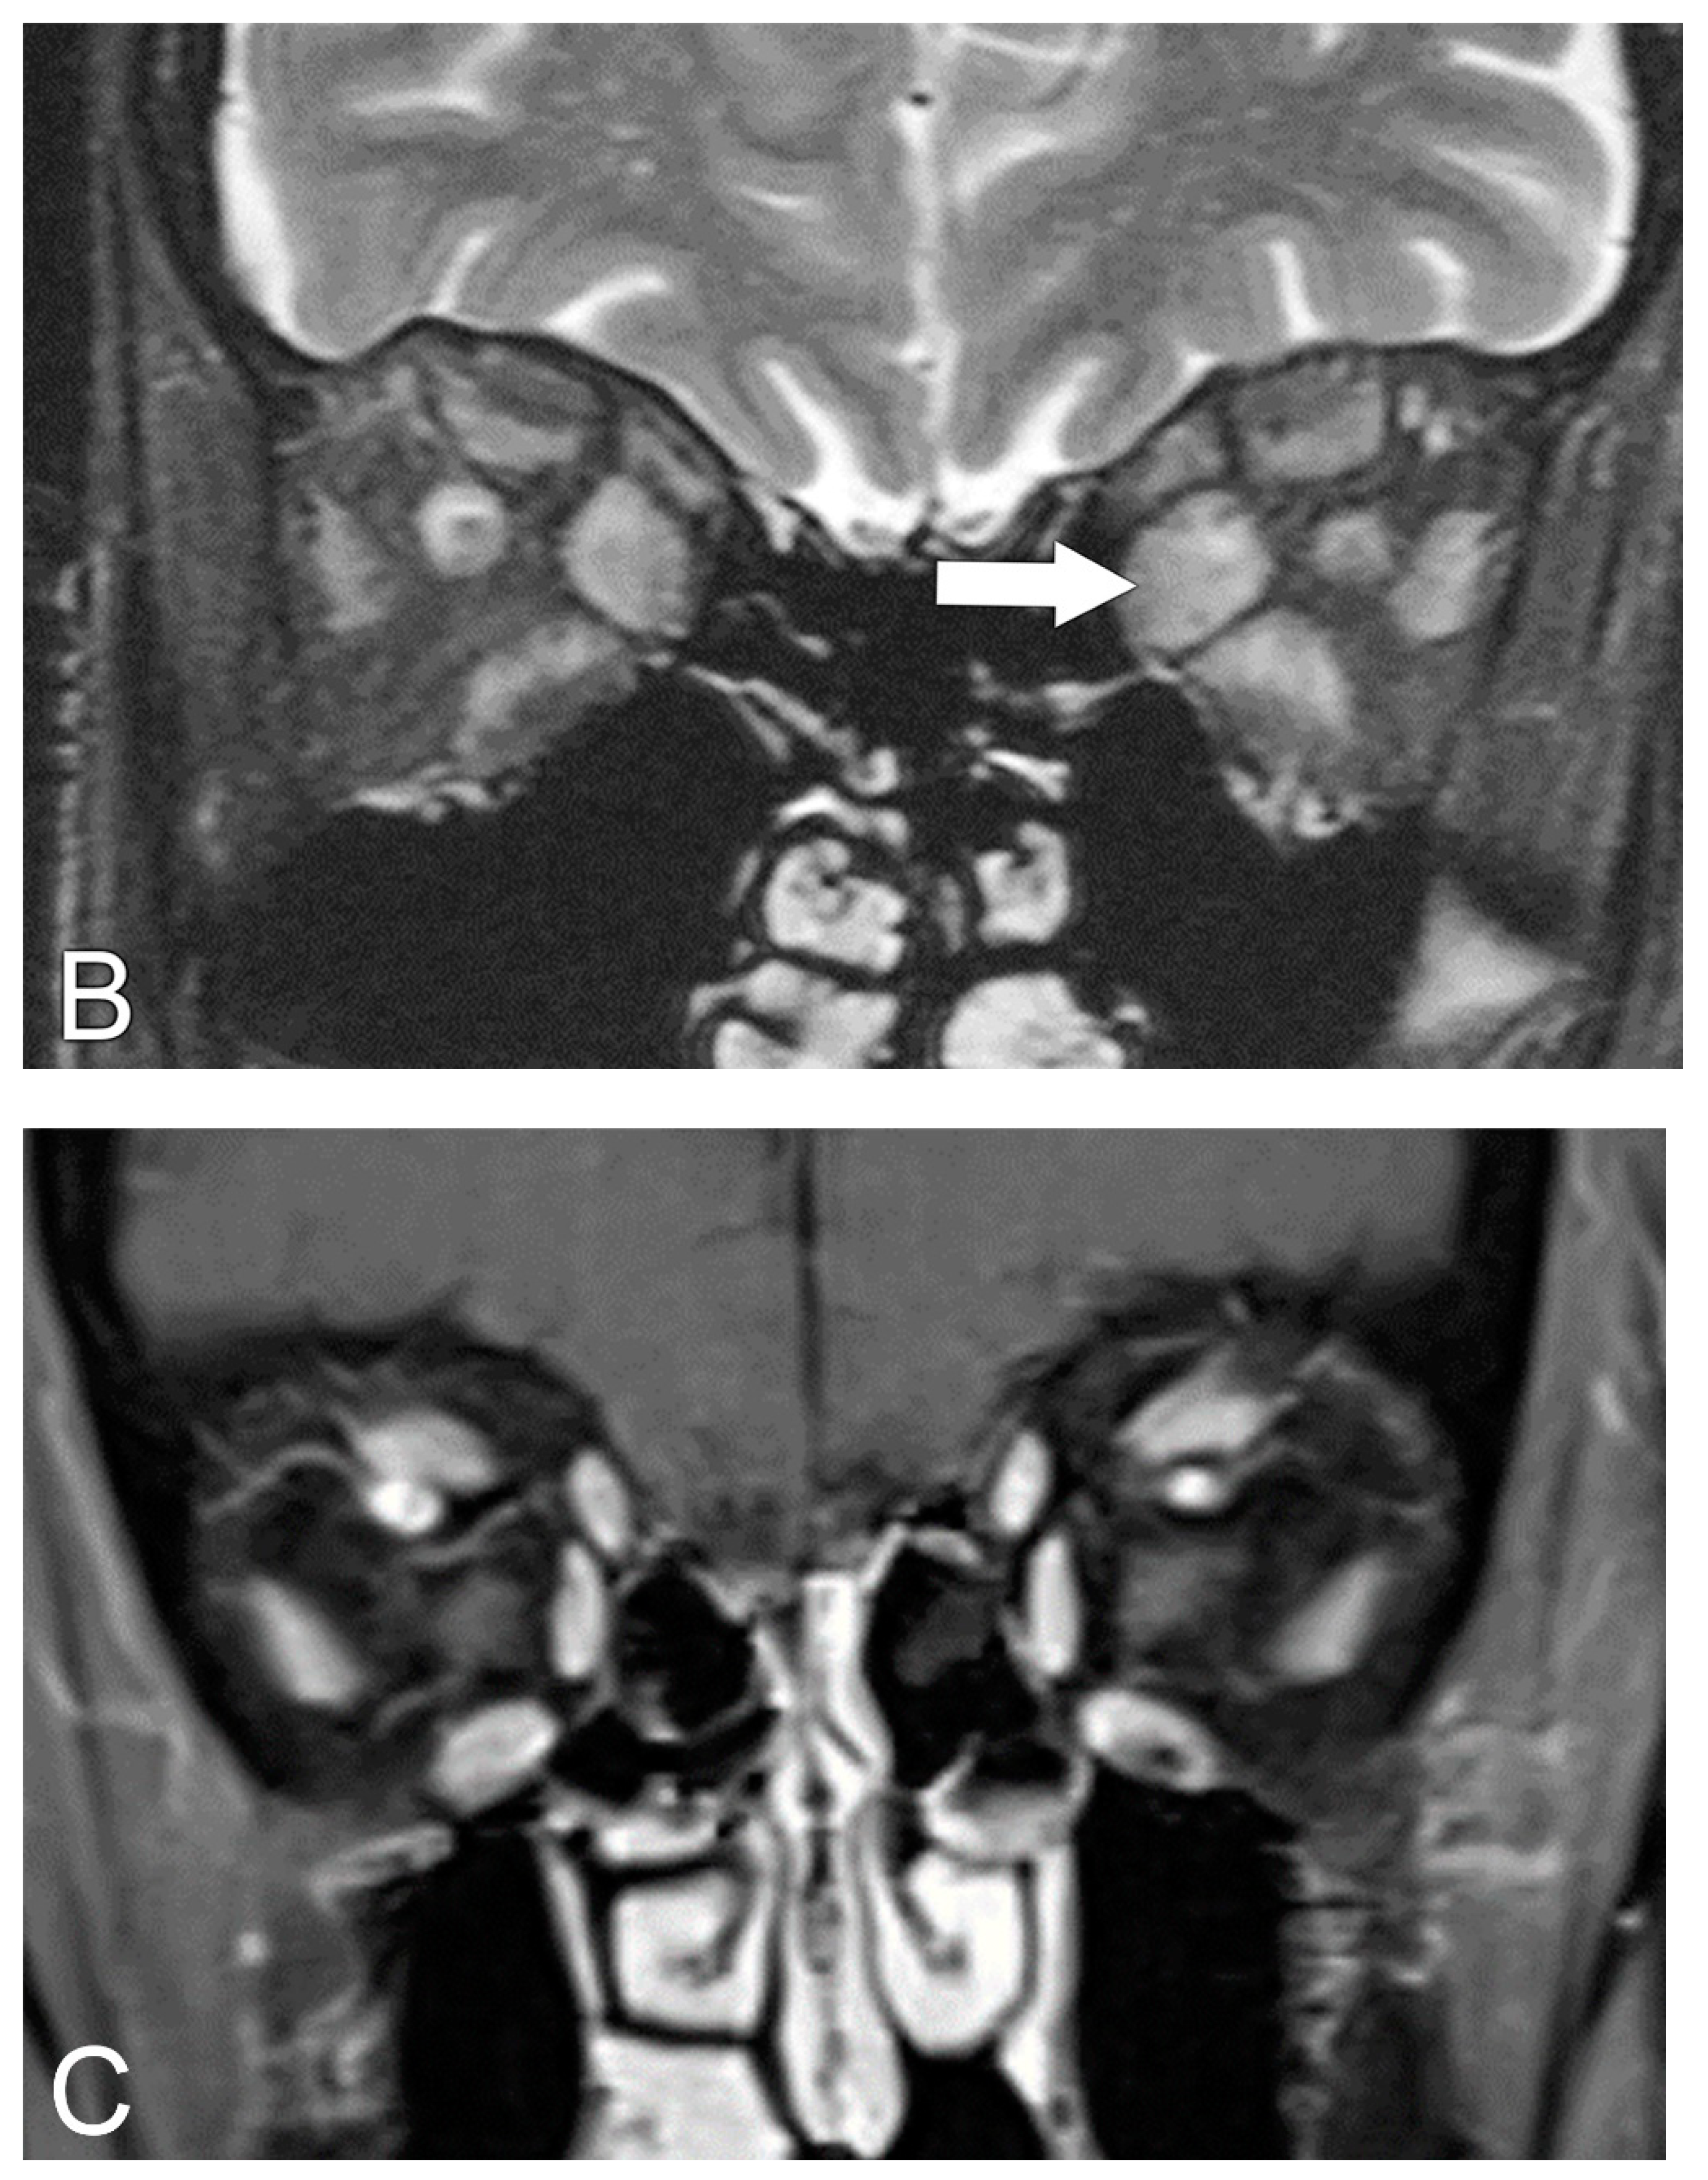

5.2. Magnetic Resonance Imaging (MRI)

5.4. Diagnosis of Compressive Optic Neuropathy (CON)